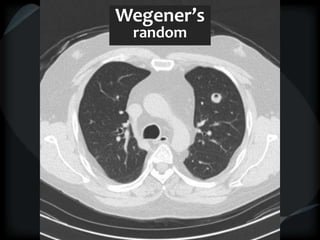

Wegener’s

random